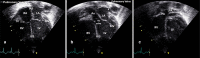

Cardiac ultrasound techniques are increasingly used in the neonatal intensive care unit to guide cardiorespiratory care of the sick newborn. This is the first in a series of eight review articles discussing the current status of "neonatologist-performed echocardiography" (NPE). The aim of this introductory review is to discuss four key elements of NPE. Indications for scanning are summarized to give the neonatologist with echocardiography skills a clear scope of practice. The fundamental physics of ultrasound are explained to allow for image optimization and avoid erroneous conclusions from artifacts. To ensure patient safety during echocardiography recommendations are given to prevent cardiorespiratory instability, hypothermia, infection, and skin lesions. A structured approach to echocardiography, with the same standard views acquired in the same sequence at each scan, is suggested in order to ensure that the neonatologist confirms normal structural anatomy or acquires the necessary images for a pediatric cardiologist to do so when reviewing the scan.